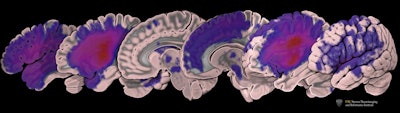

The open-source dataset is known as the Anatomical Tracings of Lesions After Stroke (ATLAS). Through this resource of manually segmented lesions and metadata, the researchers hope to identify biological markers that could predict which rehabilitation therapies will produce the best response.

Typically, researchers manually draw boundaries around stroke-related lesions. With the help of new algorithms, an automated segmentation process would be able to analyze more images.